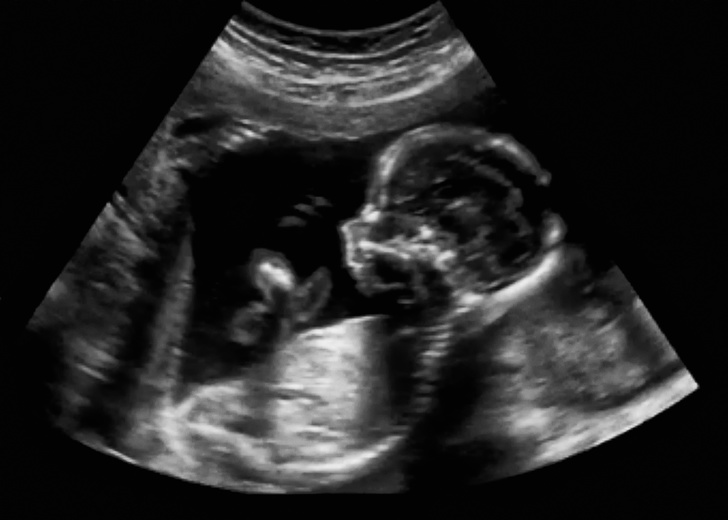

2. Ultrahang

Egy másik elmélet szerint az ultrahang hatással lehet a még meg nem született gyermekek agyára. Az ultrahang által nagyobb a lehetősége a balkezesség kialakulásának a későbbiek során.